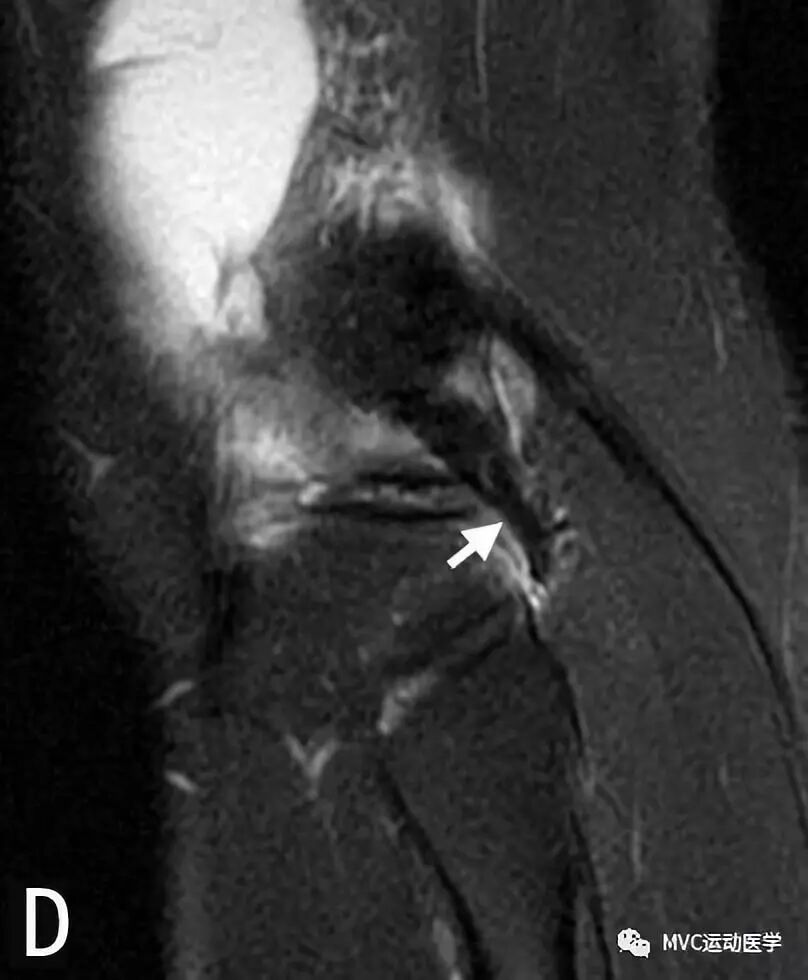

八、半月板股骨韧带

半月板股骨韧带分为两束,两束都起于外侧半月板后角,与PCL并行斜向止于PCL的股骨附着区域。Humphrey束位于PCL前方,PCL后方是Wrisberg束。Wrisberg束较为粗大,直径可达PCL的一半,出现率为74%,Humphrey束出现率为69%,两束同时出现的概率可达50%。在MRI上,Humphrey束出现率为4%,Wrisberg束出现率为80%,可同时观察到双束的仅占1%。Humphrey束在矢状位片上最易观察,也可出现在冠状位上;Wrisberg束在后冠状位上容易观察。

A:冠状位MRI显示外侧半月板后角(白色粗箭头)与Wrisberg韧带(白色细箭头),P代表后交叉韧带

B:矢状位MRI连续扫描,黑色箭头所指为Wrisberg韧带

C:矢状位MRI连续扫描,黑色箭头所指为Wrisberg韧带

D:矢状位MRI连续扫描,黑色箭头所指为Wrisberg韧带,白色箭头所指为Humphrey韧带;

半月板股骨韧带的半月板附着处易与外侧半月板后角的撕裂相混淆。韧带与半月板之间有液体或脂肪填充,可在MRI表现为由前上至后下的斜行撕裂。当膝关节外旋时,半月板股骨韧带与半月板之间的间隙更加明显,Wrisberg束比Humphrey束更易被误认为是半月板撕裂。